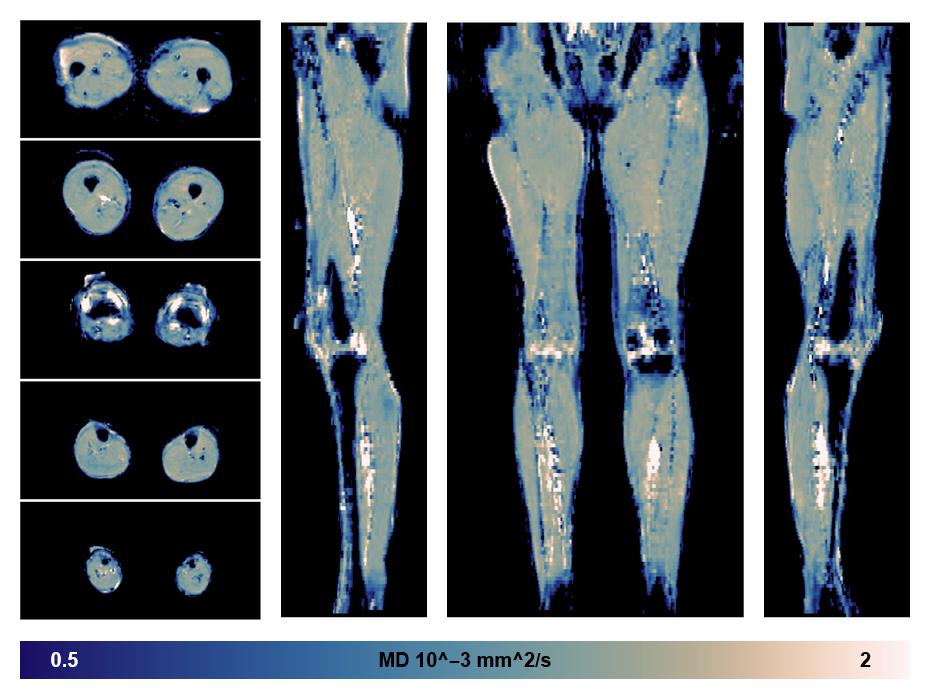

• Mean diffusivity

IVIM corrected whole leg muscle mean diffusivity obtained from diffusion tensor imaging.